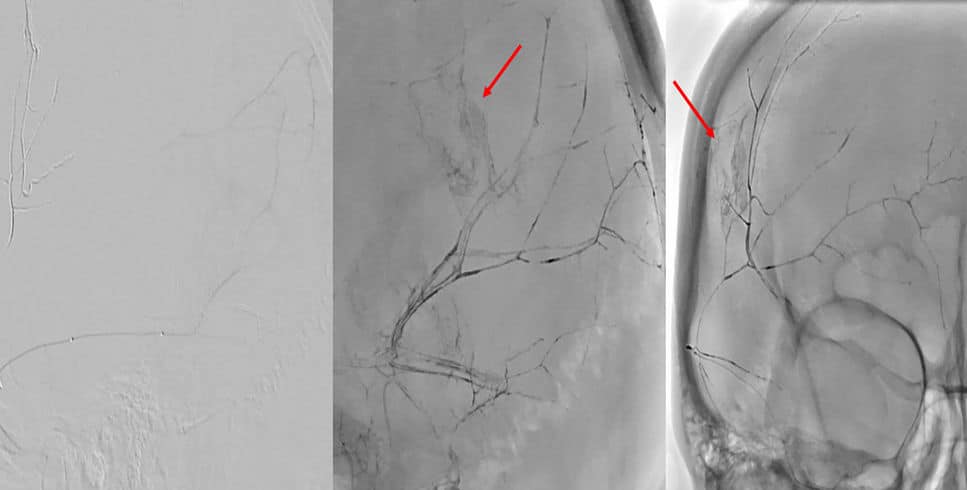

Através dessa punção, cateteres são navegados sobre controle em tempo real por raios-X até a artéria carótida externa, de onde se origina a artéria meníngea média.

De lá, cateteres ainda mais finos e delicados são navegados até a artéria a ser embolizada. Depois de uma cuidadosa análise da anatomia local, um líquido embolizante (cola, Squid® ou Onyx®) ou micropartículas são usados para ocluir a artéria.